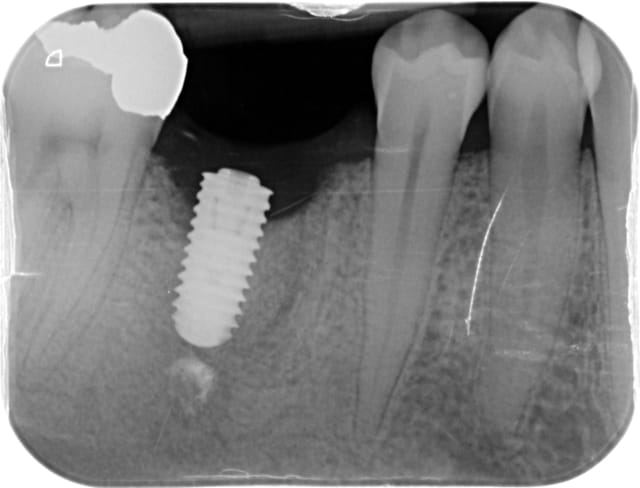

Septembre : je pose l'implant, tout se passe bien, serré à 50, j'aurais pu l'enfouir davantage.

Janvier 2015 : oh la mauvaise surprise : une image en cupule en mésial, et une image angulaire en distal. De plus la gencive était légèrement percolée, on voyait la tête de vis de couverture.

je ne suis pas spécialiste des Axiom Anthogyr, mais c'est un implant à poser en principe en sous crestal...

là tu l'as posé juxta voir supracrestal...

il me semble avoir lu sur nonol que certains utilisateurs de l'axiom avaient quelques problèmes de cratérisation de leurs implant s'ils ne les enfouissaient pas assez, ce qui semble être aussi ton cas ici...

Change d'implant, des grosses spires jusqu'en haut c'est emmerdant.

C'est pire que ça, il y a une spire non synchronisée avec le reste au niveau du col pour augmenter les contraintes à ce niveau ;)

Par contre, les Axiom Anthogyr, doivent être posés en sous crestal de 1mm au moins, sans échauffement au forage bien sur.

L'implant est un 4x10mm